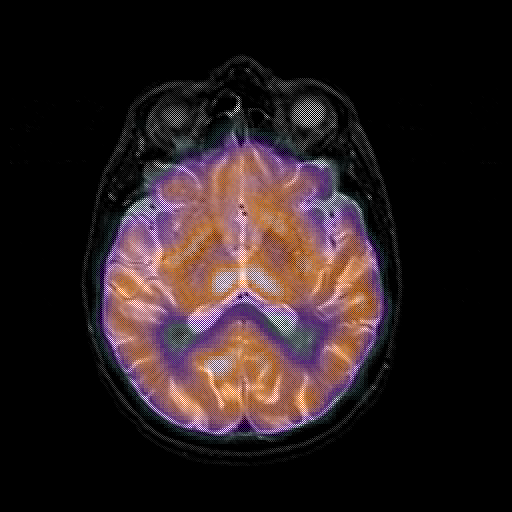

overlay 1: Slice 28

Slice 28

MRCBFCBF with

T1PDT2T1PDT2